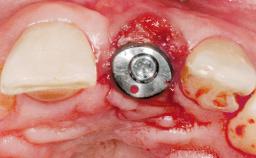

Type of Implants One-Piece

Attachment One-Piece

Abutment Type Standard

Prosthesis Type FDP

Loading Protocol Conventional or early

Retention Screw-retained Screw-retained

Provisional Implant-Supported Prosthesis Prosthodontic margin > 3 mm apical to mucosal margin Prosthodontic margin > 3 mm apical to mucosal margin